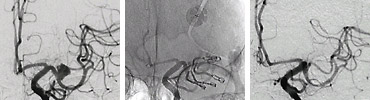

DSA(脳血管撮影)

カテーテルを血管内に挿入して脳血管を造影する侵襲のある検査法で脳血管などを鮮明に描出できます。

脳外科手術やカテーテル治療が必要かどうかを判定する場合やそれらの治療をより安全に行うために必要です。